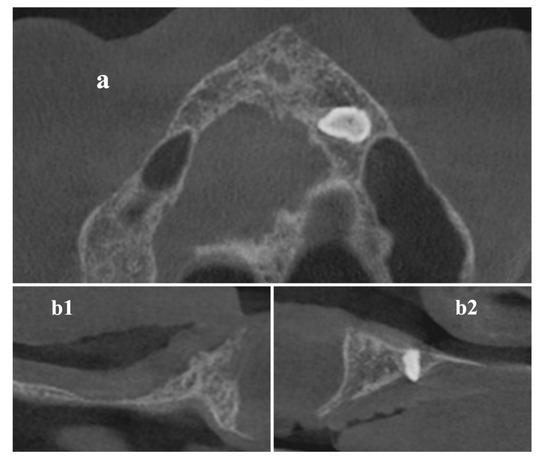

Digital Imaging and Communications in Medicine (DICOM) data of the maxilla (Figure 1) were acquired by a Cone Beam Computerized Tomography (CBCT) scanner (Orthophos XG 3D Ceph, Dentsply Sirona Italia Srl, Roma, Italy) and imported into the 3DSlicer software (www.slicer.org) [16,17,18].

Figure 1. Cone-Beam-Computed-Tomography (CBCT) axial (a) and cross-sectional (b1,b2) images before surgical procedure.